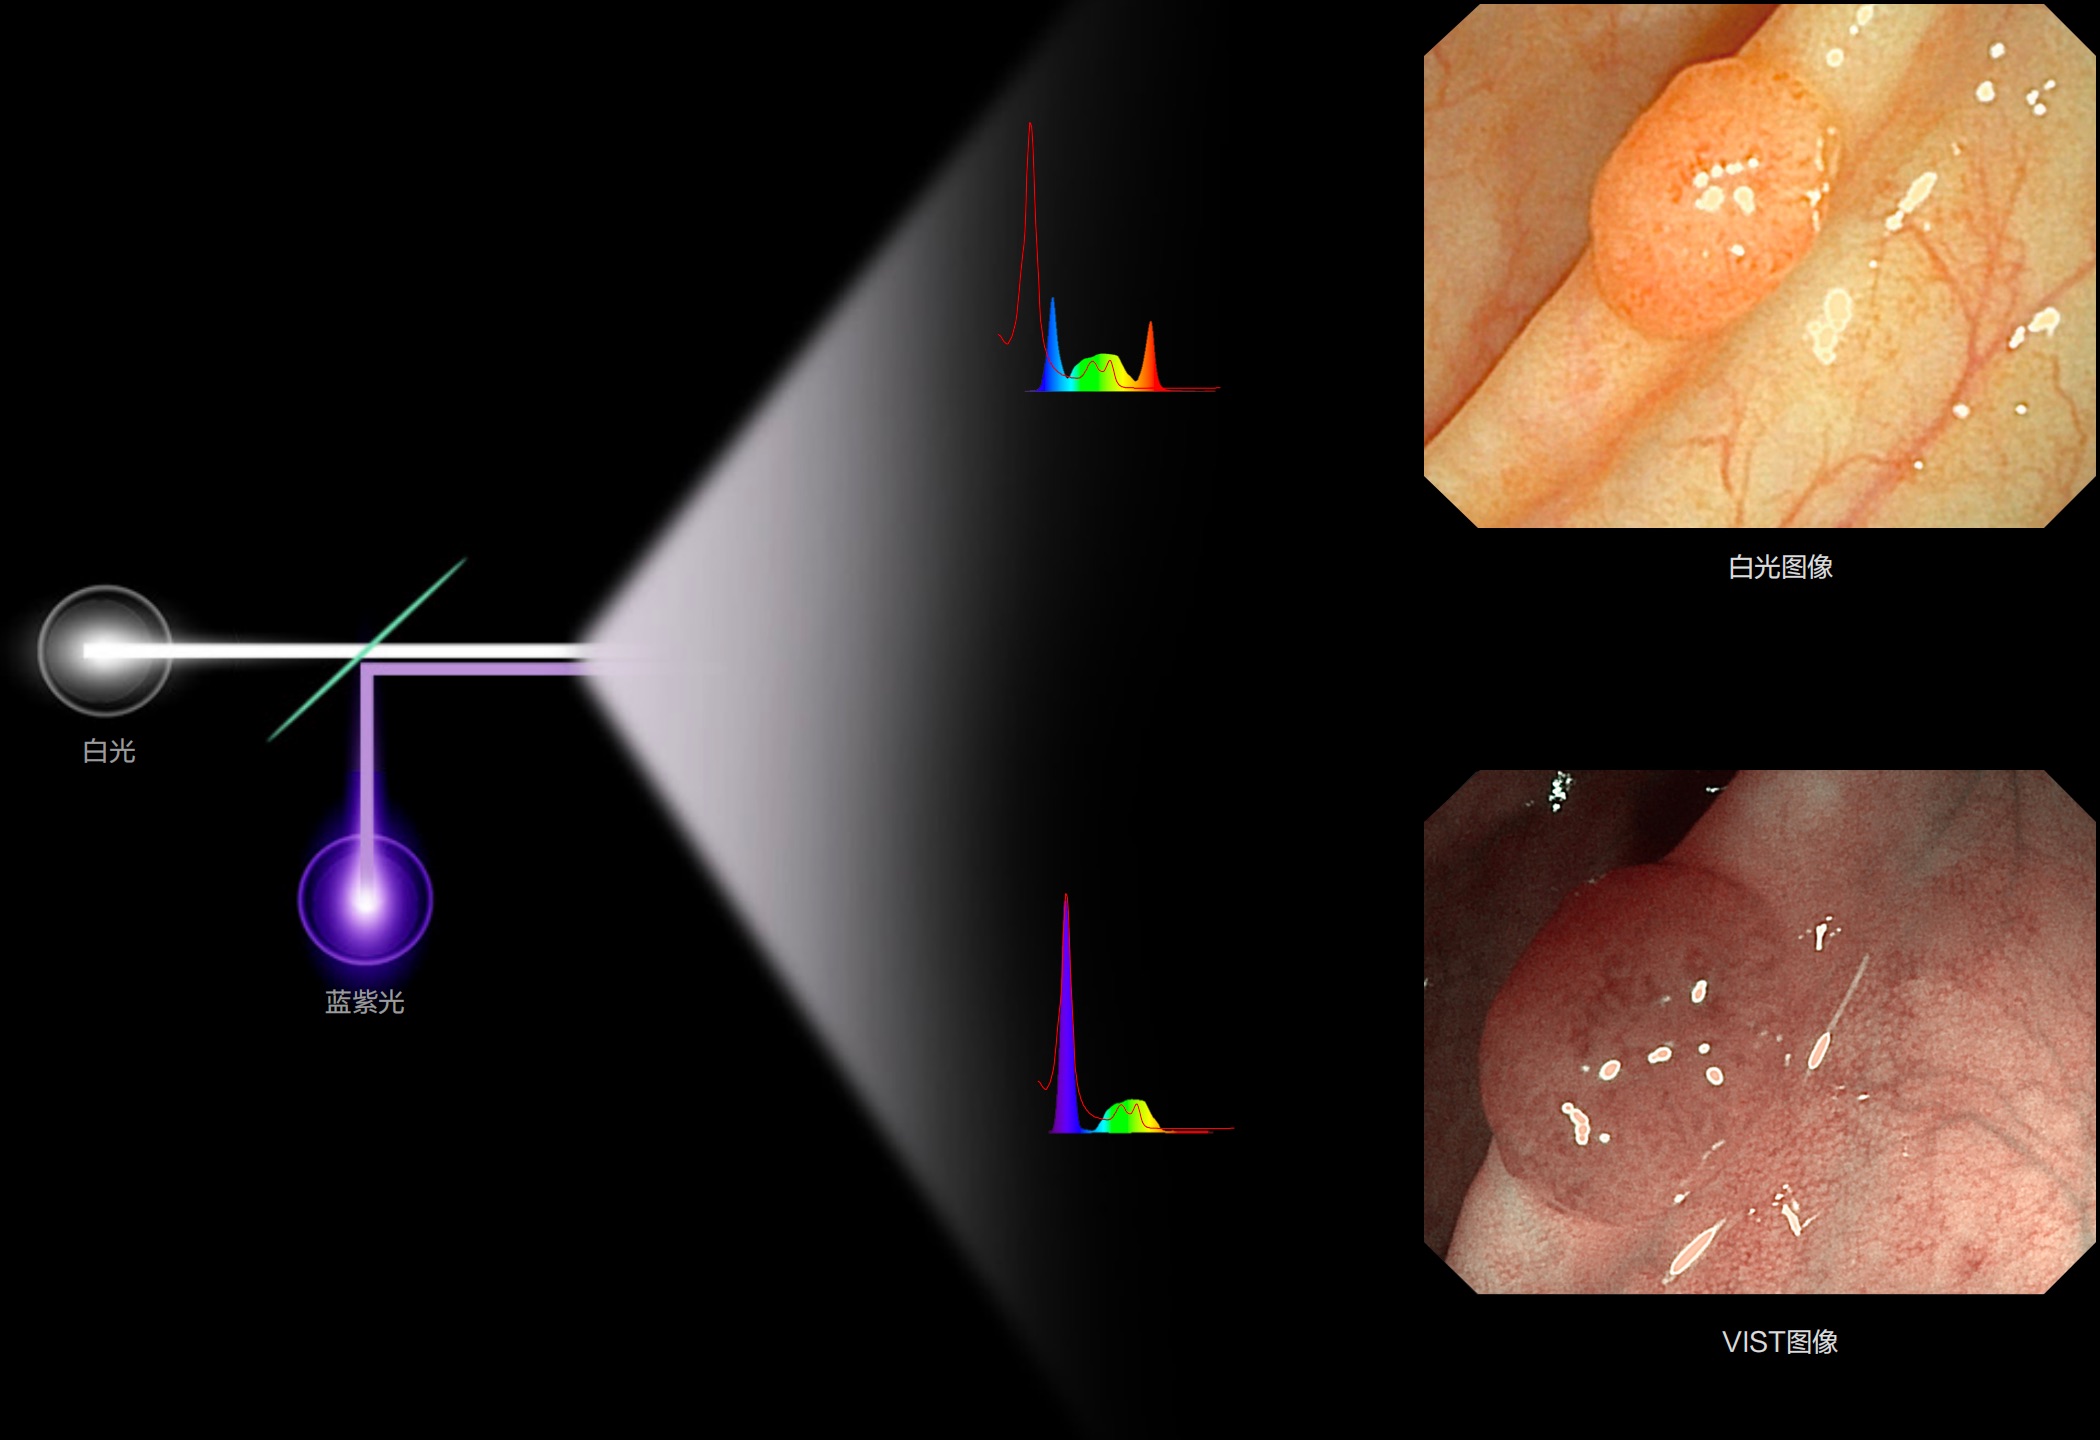

(Spectral Focused lmaging, SFI)

能够凸显黏膜浅层和中层血管轮廓,适用于中、远景观察下的病灶识别和早癌筛查。

照明光谱

光谱提取

光谱提取能量汇聚

RGB图像重建

染色模式显示

白光图像

SFI图像